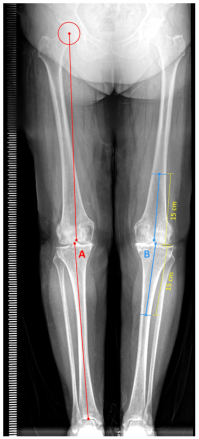

The patients' age, height, weight, and body mass index were recorded. Lower extremity dominance was determined by the ball-kicking test.[29] Clinical data related to knee OA included the duration and severity of knee pain (measured via numeric rating scale [NRS]), scores from the Western Ontario and McMaster Universities Osteoarthritis Index (WOMAC) for pain, joint stiffness, and function, as well as goniometric measurements of knee joint range of motion. Radiological assessments comprised the Kellgren-Lawrence knee OA stage and knee joint alignment, represented by the anatomical and mechanical tibiofemoral angles on standing anteroposterior full-limb radiographs. Knees were categorized by tibiofemoral joint degeneration into minimal-to-mild OA (Kellgren-Lawrence Grades 1 and 2) and moderate-to-severe OA (Kellgren-Lawrence Grades 3 and 4). Radiographic imaging was conducted with the knee in full extension. The foot and lower leg were positioned with the patella oriented anteriorly to ensure optimal centralization of the intercondylar notch, tibial intercondylar eminence, and tibial plafond. The mechanical tibiofemoral angle (TFA) was determined by measuring the angle between the mechanical axes of the tibia (the line between the center of the tibial intercondylar eminence and the midpoint of the tibial plafond) and femur (the line between the center of the femoral head and the midpoint of the intercondylar notch of femur; Figure 1).[30,31] The anatomical TFA was assessed by measuring the angle from the intersection of the anatomical axis lines drawn on the distal femur and proximal tibia (Figure 1). The anatomical axis of the distal femur was determined by a line drawn between the intercondylar notch and the midpoint on the diaphysis, located 15 cm from the lowest surface of the lateral femoral condyle. Similarly, the anatomical axis of the proximal tibia was defined by a line connecting the center of the tibial intercondylar eminence to the midpoint on the diaphysis, situated 15 cm from the uppermost surface of the lateral tibial plateau. In healthy individuals, the anatomical TFA ranges between 4° and 6°. Typically, the mechanical TFA is approximately 6° lower than the anatomical TFA.[30] Lower or negative tibiofemoral angles indicate knee varus.[31]